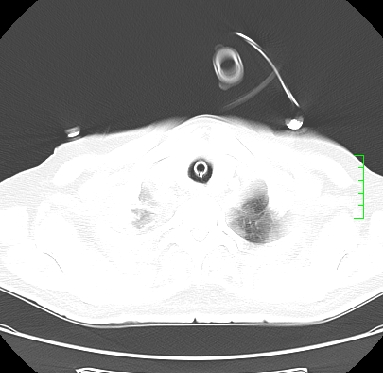

icu病人,几天都没明确诊断。m,76y,咳嗽、咳痰1周,伴气促,右胸痛入院,pe:t38.3c p135 r25 bp135/85。双肺可闻及大量湿罗音,心、腹未见明显异常。诊断:1心衰?2肺部感染?3冠心病?

9号平片

11号ct